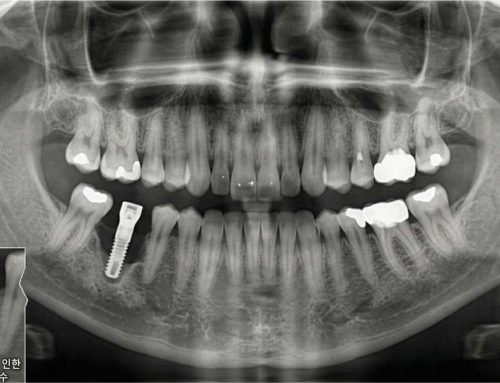

임플란트는 한 개 또는 여러 개의 치아를 대체할 수 있는 영구적인 솔루션으로, 기능성과 심미성을 동시에 회복할 수 있게 도와줍니다. 그러나 임플란트 시술은 성공률에 영향을 미칠 수 있는 몇 가지 조건에 의해 위험해질 수 있습니다.

특히, 이갈이(Bruxism)는 임플란트 성공 여부에 중요한 영향을 미칠 수 있는 요인으로 꼽힙니다. 이번 포스팅에서는 이갈이가 임플란트에 미치는 영향과 이에 대한 예방법, 그리고 올바른 치료 옵션에 대해 알아보겠습니다.

임플란트 성공의 핵심은 골융합(Osseointegration) 과정입니다. 이는 임플란트가 턱뼈와 완전히 결합하여 안정성을 확보하는 과정으로, 수개월이 소요될 수 있습니다. 하지만 이갈이로 인해 다음과 같은 문제가 발생할 수 있습니다.

골융합(Osseointegration) 과정 동안 치아와 임플란트에 과도한 압력이나 스트레스가 가해지면 뼈와 임플란트의 결합이 약화되어 실패할 가능성이 높아집니다.

2. 임플란트 파손

반복적인 이갈이로 인해 임플란트 크라운(보철물)이나 어버트먼트(지대주)가 손상되거나 파손될 수 있습니다.

3. 치조골 손실

턱뼈에 가해지는 지속적인 압력은 뼈 흡수를 가속화하여 임플란트를 지지하는 치조골을 약화시킬 수 있습니다.